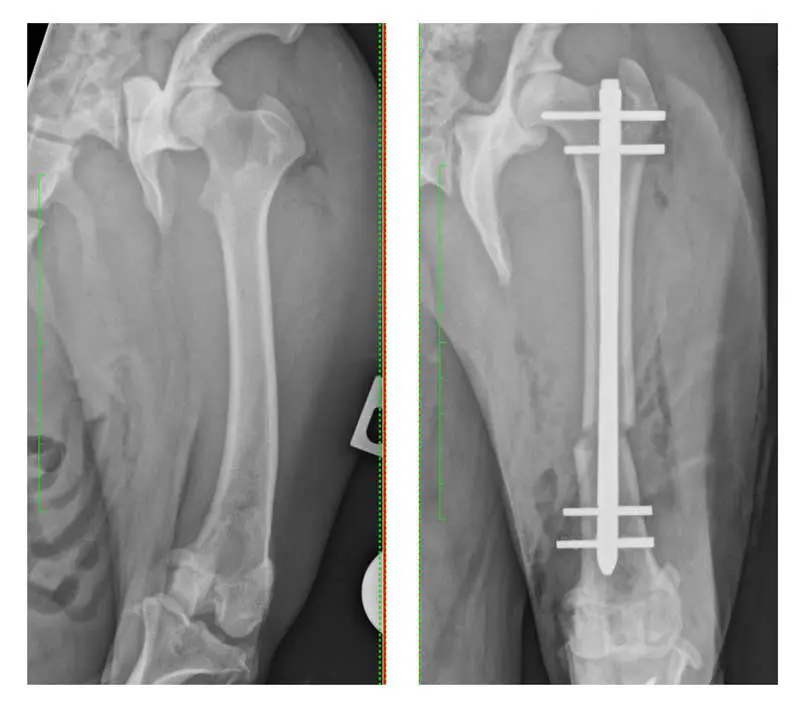

Femoral deformity plays a central role in many cases of PL. Swiderski and Palmer (16 stifles in 2007) and Brower et al (66 stifles in 2017) described the retrospective outcomes for dogs undergoing correction of distal femoral varus deformity (Figure 3) as a component of management of medial PL.

Lee et al (2020) further characterised the correlation between PL and distal femoral varus using a cadaveric study, identifying an anatomical lateral distal femoral angle of more than 103° as the severity of varus beyond which deformity correction should be considered.

Given the nature of the data, this should be considered a pragmatic threshold, rather than an absolute indication. An added complexity is present, as femoral deformity is often multiplanar, involving combinations of varus and torsion, and 3D imaging is more sensitive for identifying abnormal anatomy. Brower et al (2017) highlighted the role of CT-based planning in identifying torsional deformities not evident on radiographs.

Distal femoral osteotomy allows direct correction of femoral alignment and is increasingly accepted in dogs in which deformities exist (Figure 3). Techniques include closing wedge, opening wedge and dome osteotomies, often stabilised with plate/screw combinations. Corrective osteotomy is not without risk. It increases surgical time, cost and technical demand, and complications such as delayed union or implant failure can occur. However, when performed appropriately, it addresses the root cause of patellar maltracking.